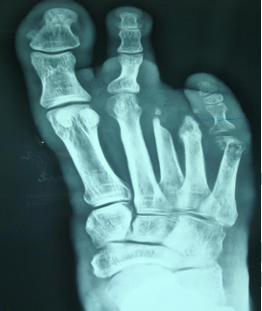

A total of 21 patients with diabetic foot osteomyelitis were included in this study. There were 14 males [66.67%] and 7 females [33.33%]. The average age for males was 49.2 years with age ranging from 39 years – 66 years and average age for females was 51.5 years with age ranging from 41 years – 64 years. 20 patients [95.23%] had unilateral osteomyelitis and one patient [4.76%] had bilateral osteomyelitis. 19 patients [90.48%] with osteomyelitis had underlying ulcers [Figure 1] and these were type 3 diabetic foot complication whereas 2 patients [9.52%] did not have ulcers but abscess and they belonged to type 1 diabetic foot

Figure 1 showing a non healing ulcer with abscess in diabetic foot.

Figure 2 showing the radiograph of patient in figure 1. Note this is type 1-B diabetic foot osteomyelitis according to Amit Jain’s classification of diabetic foot osteomyelitis affecting the 5th metatarsal.